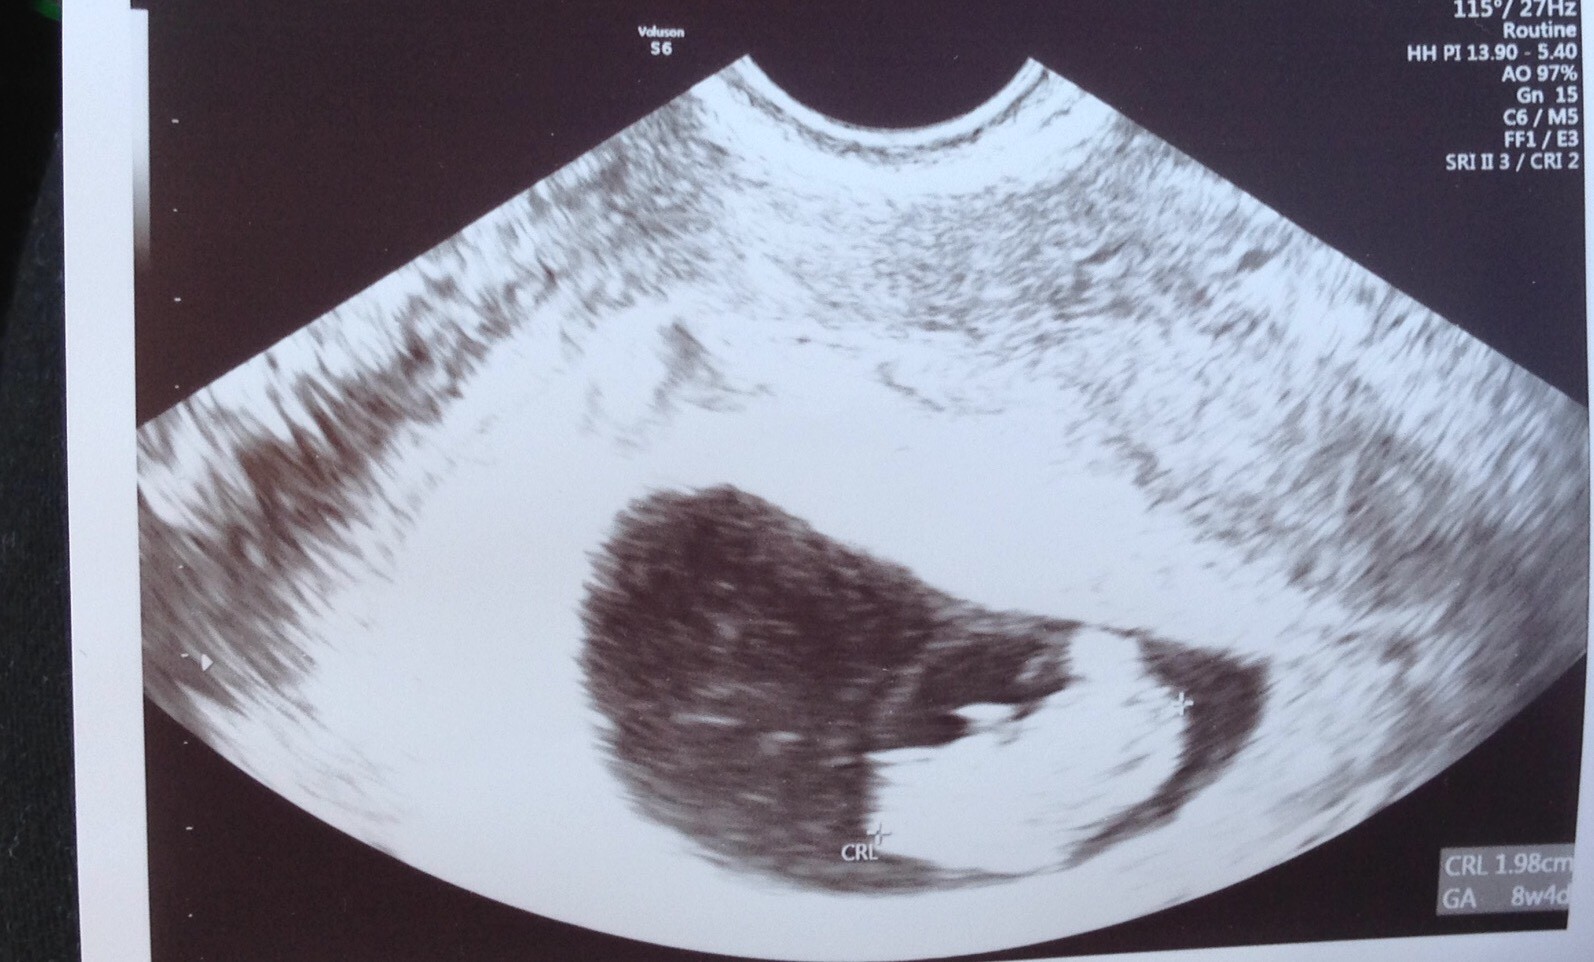

Dziewczyny mam pytanie ale pewnie zaraz mnie zjecie ze nie powinnam tak gadac itd itp ale chcialabym wiedziec zeby nie panikowac jakby juz cos

Czy jesli zaczelabym krwawic-ronic to mam gnac do szpitala czy spokojnie przetrzymac do poniedzialku?